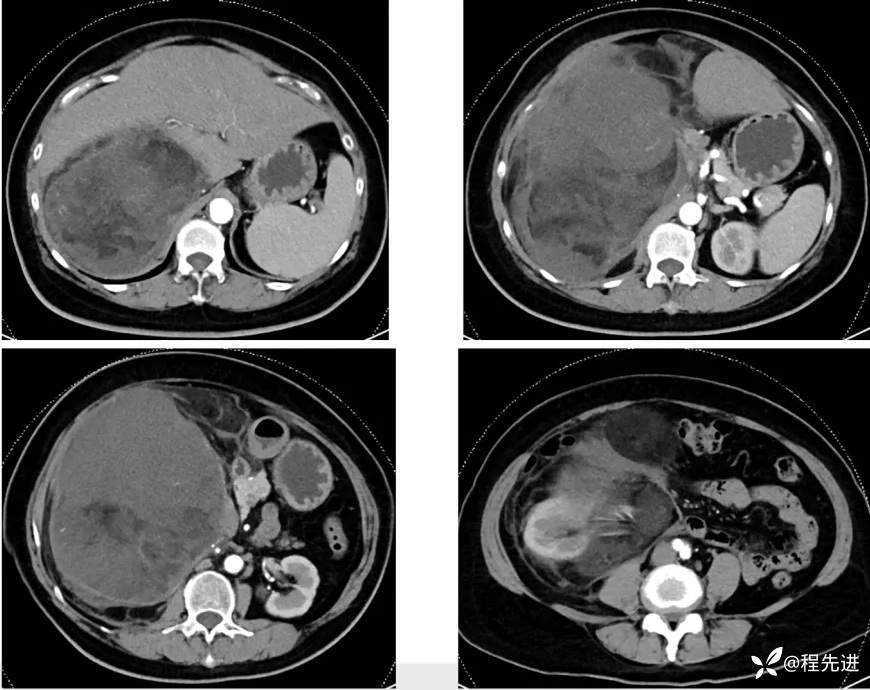

【主诉】:腹胀2月余,发现腹腔占位10天

【现病史及既往史】:患者2月余前出现腹胀,胃反酸,无寒战发热胸闷胸痛、恶心呕吐、腹痛腹泻等不适伴随症状。10天前患者自查发现腹腔占位

【检查】: